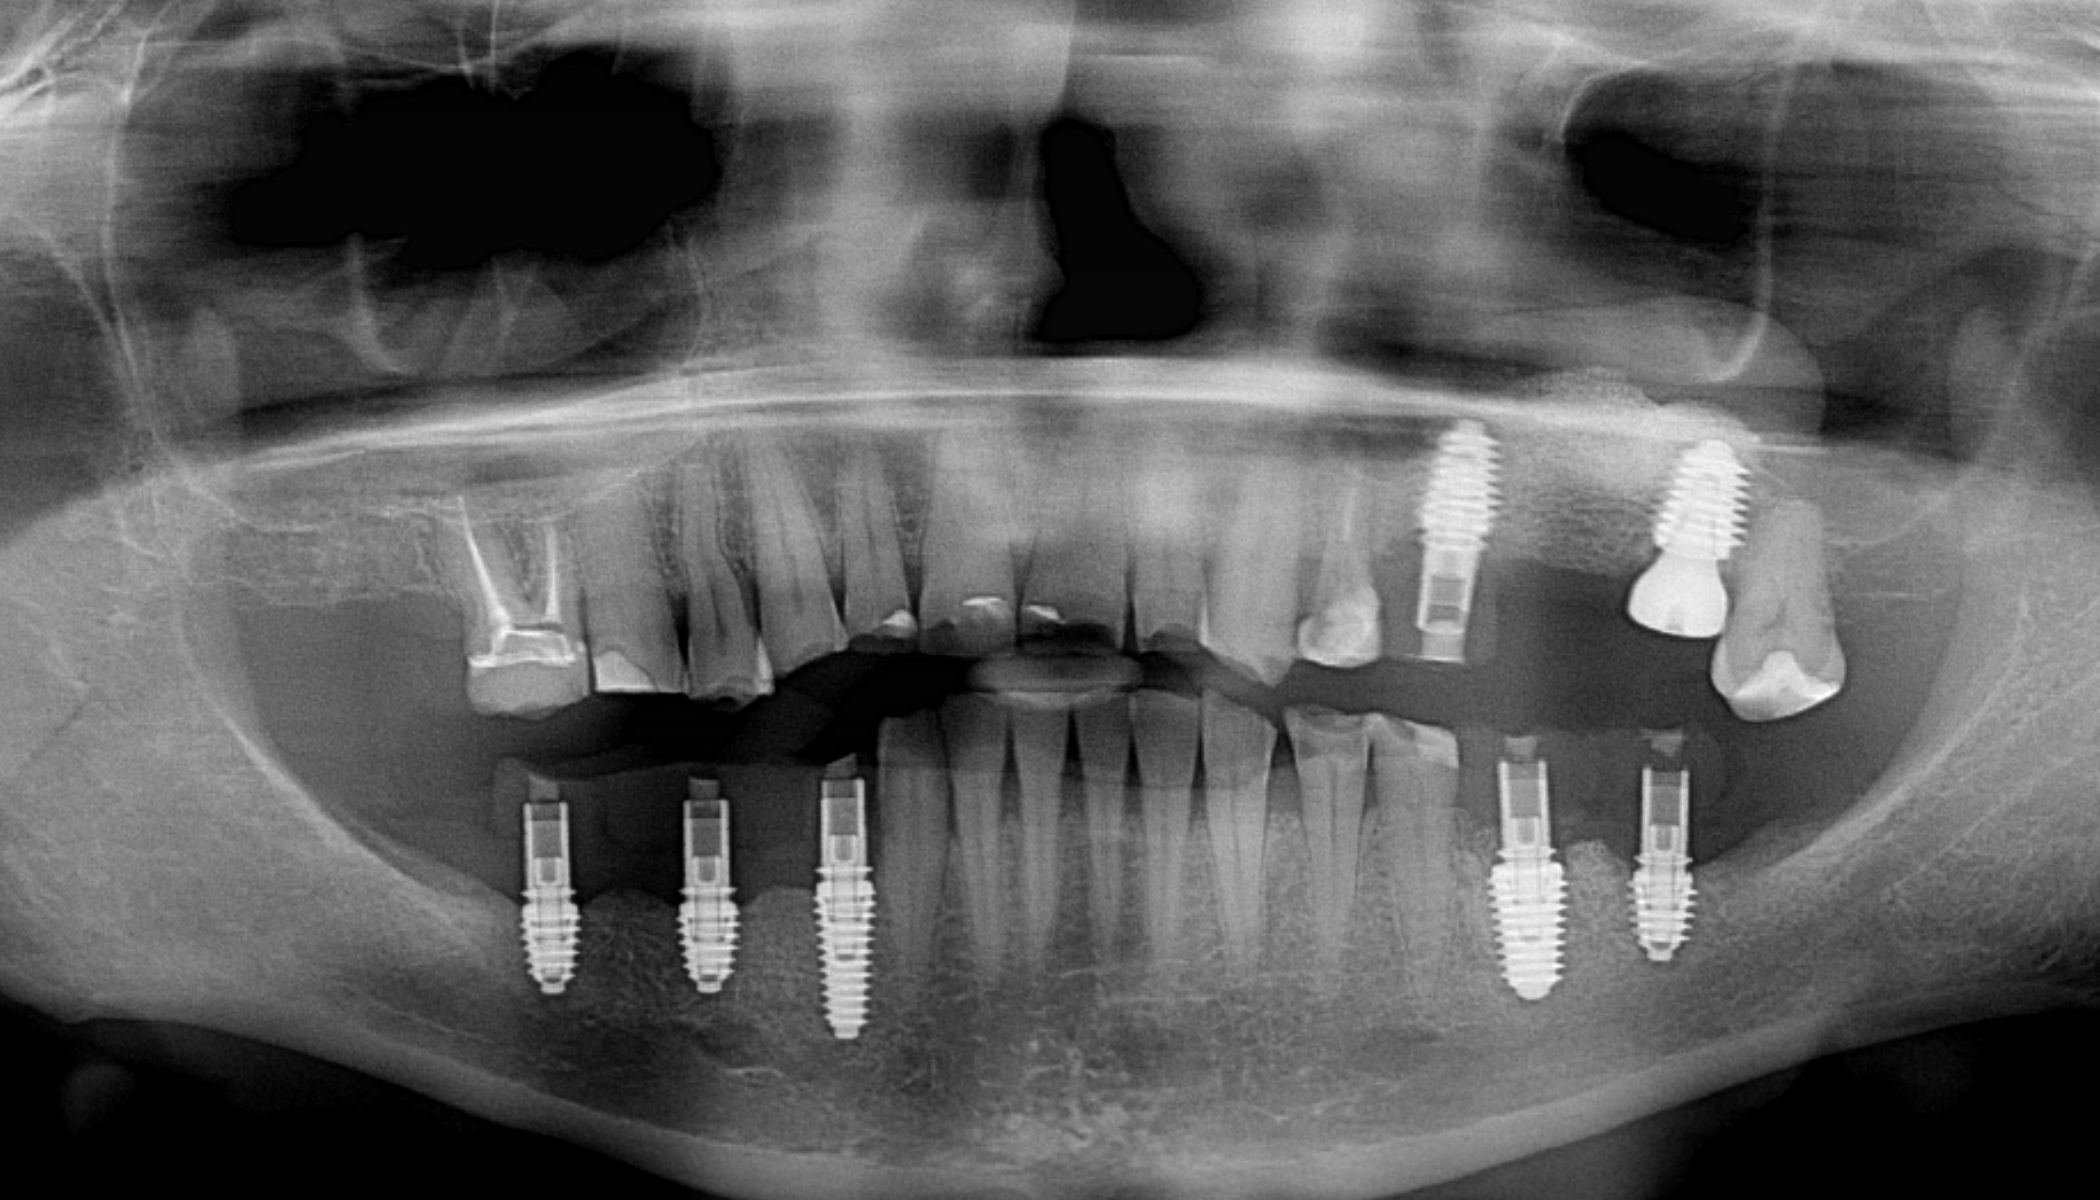

На первом, хирургическом этапе были удалены несостоятельные зубы и установлены имплантаты. Затем изготовлены временные коронки с опорой на установленные импланты. Через три месяца после имплантации зубов был проведён второй этап — диагностическое моделирование. В рамках этого этапа мы смоделировали будущую улыбку пациентки и изготовили временные реставрации на все зубы верхней и нижней челюстей.

На третьем этапе, после двухмесячного периода адаптации, временные реставрации были заменены на постоянные безметалловые конструкции. В результате комплексного подхода удалось полностью восстановить эстетику и функциональность зубочелюстной системы. Пациентка вновь обрела полноценную улыбку и улучшенную способность пережёвывания пищи. Это положительно сказалось на качестве её жизни. Таким образом, проведённое лечение эффективно решило проблему отсутствия жевательных зубов и изменения формы остальных, улучшив как внешний вид, так и функциональные параметры ротовой полости.